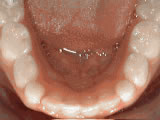

Non-braces treatment

Before

AfterSometimes braces are not needed to get noticeable improvements in tooth alignment. This patient was first seen at age seven for crowding of the lower permanent teeth. A procedure was performed to reduce the width of the adjacent baby teeth and the permanent incisors aligned on their own in nine months.